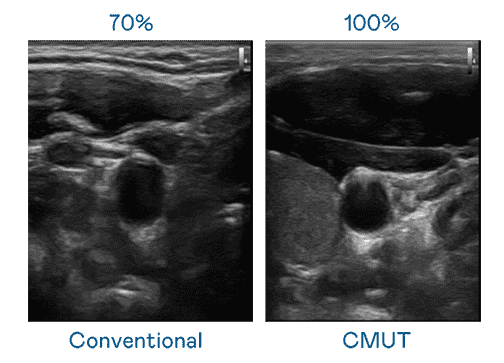

CMUT 技术是一种用电容式微机电元件来产生超音波讯号的技术。。。与传统 PZT 压电式技术相比,,,,CMUT 频宽增加 30%,,更宽频的超音波讯号让影像解析度大幅提升,,,是实现高影像品质医疗超音波扫描、、、促进精准医疗发展的关键技术。。。。

大频宽带来超清晰影像

超音波影像的解析度高低,,首先取决于探头能发出的讯号频宽。。。尊龙z6 CMUT 可提供高清晰的超音波讯号,,,提供高频宽、、、、高灵敏度、、、、影像纹理细节更高的超音波影像,,,协助医护人员缩短影像判读时间及利用精准的医疗影像进行诊断。。。